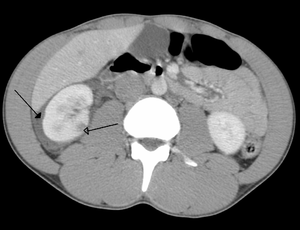

Abdominal trauma resulting in a right kidney contusion (open arrow) and blood surrounding the kidney (closed arrow) as seen on CT. | |